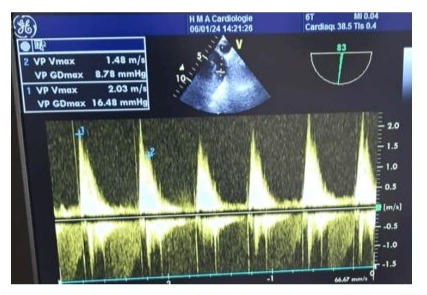

64-year-old female, with medical history of hypertension, hyperlipidemia, symptomatic mitral insufficiency presented initially with a history of repetitive episodes of acute cardiac insufficiency, worsening dyspnea on exertion, orthopnea, paroxysmal nocturnal dyspnea. Despite optimization of medical therapy with sacubitril/valsartan, spironolactone, dapagliflozin, high-dose furosemide, bisoprolol, her symptoms continued to deteriorate. In her hospitalization in cardiology, the physical examination revealed signs of congestive heart failure, including elevated jugular venous pressure, bibasilar crackles, and a pansystolic murmur loudest at the apex radiating to the axilla. Transthoracic Echocardiography (TTE): Showed severe mitral regurgitation with a flail posterior leaflet, left ventricular dysfunction with an ejection fraction of 50%, tele-systolic diameter at 44mm, dilated left atrium and ventricle, and pulmonary hypertension with an estimated systolic pulmonary artery pressure of 60 mmHg. Transesophageal Echocardiography (TEE) has confirmed TTE findings and provided detailed assessment of the mitral valve pathology, including the mechanism and severity of regurgitation, as well as assessment of the tricuspid valve and right ventricular function. Given the severity of her symptoms and the progressive nature of her disease despite optimal medical therapy, she was scheduled for surgical intervention 3 months later after stabilization and complete decongestion with the addition of higher doses of furosemide. The plan involved mechanical mitral valve replacement given that mitral valve repair was deemed unfeasible based on the TEE data and the surgical team's experience and tricuspid annuloplasty to address the valvular pathology and alleviate symptoms of heart failure. The patient underwent cardiac surgery via median sternotomy with cardiopulmonary bypass. Mechanical mitral valve replacement (size 29) and tricuspid annuloplasty using a 32-mm semi-rigid annuloplasty ring were performed. TEE provided detailed intraoperative assessment of the mitral and tricuspid valves, confirming the severity of regurgitation (Figure 1) (video 1), mechanism of valvular dysfunction, and the need for surgical intervention. It also allowed for real-time monitoring of cardiac function and assessment of the adequacy of the surgical repair (Figure 2,3) showing a reduction in sub aortic velocity-time integrals (VTI), indicative of left ventricular dysfunction and pulmonary hypertension through the analysis of the pulmonary regurgitation velocity. With a cross-clamp time of 60 minutes and a cardiopulmonary bypass (CPB) duration of 120 minutes however, the weaning from cardiopulmonary bypass was complex, requiring central extracorporeal membrane oxygenation (ECMO) support. Progressive doses of inotropic support including epinephrine Corotrope, norephedrine, and inhaled nitric oxide were administered due to persistent hemodynamic instability with evident signs of pulmonary hypertension including a hypokinetic and dilated right ventricle, paradoxical septum, significant pulmonary regurgitation with elevated mean pulmonary artery pressure (MPAP), systolic pulmonary artery pressure (SPAP), and diastolic pulmonary artery pressure (DPAP), despite high doses of inotropes and pulmonary vasodilators. The left ventricular function was clearly impaired with a hypokinetic left ventricle, which dilated after a few minutes of complete cessation of cardiopulmonary bypass support. Due to the inability to wean off cardiopulmonary bypass (CPB), And after verification via intraoperative transesophageal echocardiography (TEE) of the proper functioning of the mechanical valve (video 2,3,4), central ECMO was implemented with arterial cannulation at the left ventricular apex and venous atrial cannulation, aiming for bridge to recovery and to prevent recurrent pulmonary edema episodes on peripheral ECMO, given the high filling pressures estimated by deceleration time and the E/Vp ratio and the falling ETT has shown an absence of holosystolic aortic valve opening under veno-arterial ECMO after failure to wean from cardiopulmonary bypass, indicating severe ventricular dysfunction and the non-contribution of the heart to the cardiac output generated by mechanical circulatory support associated to proper function of the Saint-Jude-Medical bileaflet valve with a low mean transvalvular gradient, indicative of postoperative left ventricular dysfunction. (Figure 4,5)Unfortunately, the patient developed significant bleeding, the advanced laboratory tests, which took time to arrive because we do not have localized laboratory devices to guide initial therapeutic strategies, a massive transfusion of platelets, fresh frozen plasma, packed red blood cells and fibrinogen concentrates has been performed, prothrombin complex concentrates were not available. Given the hemostatic disorders with laboratory evidence of hypofibrinogenemia and thrombocytopenia, suggestive of coagulopathy and consumptive coagulopathy secondary to surgical trauma and cardiopulmonary bypass, and the need for a reoperation was not taken, the ECMO pump flow continued to decline despite increasing, due to venous line collapse following a decrease in volume (video 5,6). Despite aggressive resuscitative efforts, she succumbed to complications and expired 24 hours after surgery.

Figure 1: Intraoperative TEE performed before CPB, showing a significant mean transvalvular gradient, indicative of grade 3-4 mitral regurgitation.

Figure 2: Pre-cardiopulmonary bypass (CPB) intraoperative TEE showing a reduction in subaortic velocity-time integrals (VTI), indicative of left ventricular dysfunction.

Figure 3: Pre-cardiopulmonary bypass (CPB) intraoperative TEE measurement of the protodiastolic and telediastolic gradients of pulmonary valve regurgitation by echocardiography.